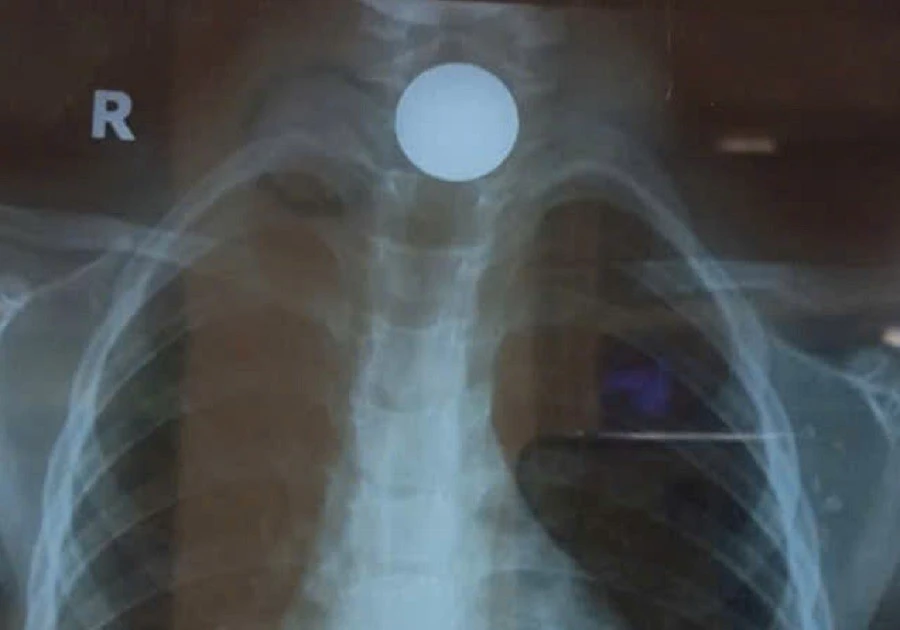

TPO - Trong lúc chơi đùa, bé trai 5 tuổi ở Vĩnh Long vô tình nuốt phải đồng xu và bị đau rát họng, khó nuốt, có lúc khò khè, thở gấp khiến gia đình vô cùng hoảng hốt. Tuy nhiên, khi đưa đi cấp cứu, phải đến bệnh viện thứ 3 bé mới được can thiệp.